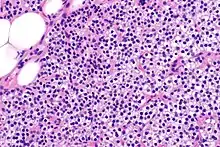

Hyperparathyroidism, in general, is caused by either tumorous growth in one or more parathyroid glands or a prolonged decrease in blood calcium levels or hypocalcaemia which in turn stimulates the production of parathyroid hormone release from the parathyroid gland.[10][11] The parathyroid gland is located beside the thyroid gland in the neck, below and in front of the larynx and above the trachea. It is composed of four glands in total that monitor blood calcium levels via the calcium sensing receptors, a g-coupled protein receptor.[12] The parathyroid glands main role is calcium homeostasis.[13][12] Histologically, these glands are composed of chief cells and oxyphil cells with the chief cell primarily responsible for the storing and release of parathyroid hormone. These cells are arranged in a pseudo-follicular pattern similar to the thyroid follicles. Keratin staining is used to image the parathyroid hormone granules.[9][14]

Parathyroid glands are normally composed of chief cells, adipocytes and scattered oxyphil cells.[27][14] Chief cells are thought to be responsible for the production, storage and secretion of parathyroid hormone. These cells appear light and dark with a prominent Golgi body and endoplasmic reticulum. In electron micrographs, secretory vesicles can be seen in and around the Golgi and at the cell membrane. These cells also contain prominent cytoplasmic adipose.[27][14] Upon onset of hyperplasia these cells are described as having a nodular pattern with enlargement of protein synthesis machinery such as the endoplasmic reticulum and Golgi. Increased secretory vesicles are seen and decreased intercellular fat is characteristic.[27][24] Oxyphil cells also appear hyperplasic however, these cells are much less prominent.